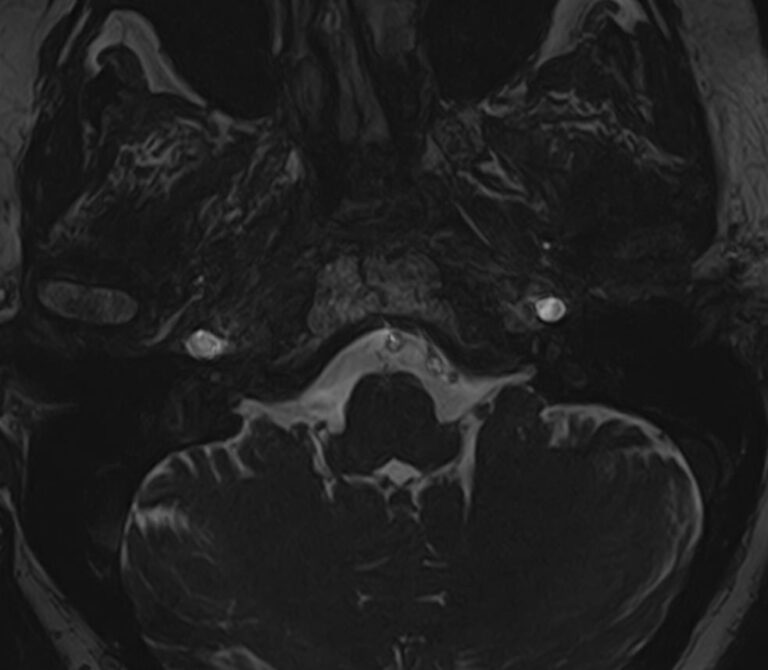

Мосто-мозжечковый угол — это пространство вблизи основания черепа в виде углубления между анатомическими образованиями: продолговатым мозгом, мозжечком и Варолиевым мостом. В этой области располагаются волокна многих черепно-мозговых нервов (например, лицевого, тройничного, преддверно-улиткового), проходят мозговые артерии и многочисленные вены мозжечка.

В мосто-мозжечковом угле часто развиваются воспалительные процессы (арахноидиты) с формированием в дальнейшем арахноидальных кист. Могут выявляться аневризмы расположенных здесь артерий. Но чаще всего в этой области образуются объемные образования, как злокачественные, так и доброкачественные, которые сдавливают расположенные там нервные волокна, кровеносные сосуды и пути ликворного оттока. Наиболее часто встречающаяся опухоль этой области — невринома преддверно-улиткового нерва. В большинстве случаев она имеет доброкачественный характер, развивается, как правило, у людей трудоспособного возраста, преимущественно у женщин. Реже встречаются менингиомы и холестеатомы мосто-мозжечкового угла.

Самым информативным, при этом быстрым и безопасным, методом диагностики опухолей мосто-мозжечкового угла на сегодняшний день является магнитно-резонансная томография с контрастированием. В клинике «Доступная медицина» проводится эффективная диагностика патологии мосто-мозжечкового угла с использованием новейшего томографа TOSHIBA VANTAGE TITAN 1,5 Тесла. Высокая мощность магнитного поля 1,5 Тесла позволяет получить подробное изображение этой труднодоступной для диагностики области в различных плоскостях.

Контрастирование проводится контрастным веществом на основе солей гадолиния (химический элемент, относящийся к редкоземельным металлам). Применяемый контрастный препарат накапливается в патологическом очаге, за счет чего при сканировании усиливается его яркость изображения. Это дает возможность выявить опухоли малых размеров (до 3 мм) и назначить своевременное лечение. Кроме того, контраст заполняет просвет сосудов, благодаря чему на снимках появляется детальное изображение сосудистой сети. Это позволяет диагностировать патологическую извитость, аневризмы, мальформации, при вазоневральном конфликте — зоны сдавления черепно-мозгового нерва кровеносным сосудом.